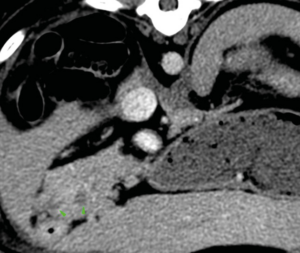

La cirugía de elección es la pancreatectomía parcial y la resección de losnódulos linfáticos (NNLL) centinelas (imágenes 3A-3I). La quimioterapia intracavitaria puede controlar la efusión por carcinomatosis secundaria, pero ofrece una respuesta paliativa de corta duración. La pancreatectomía completa o pancreaticoduodenectomía (técnica de Whipple), descritas en el perro, presentan altas tasas de morbilidad y mortalidad operatorias. La técnica de Billroth II es una opción paliativa a corto plazo en casos de obstrucción intestinal. En un estudio retrospectivo en 34 pacientes felinos con carcinoma pancreático exocrino primario la enfermedad se asoció con una historia previa de diabetes mellitus.35 El carcinoma pancreático exocrino canino se caracteriza por una alta tasa de metástasis y un pronóstico grave general.37

Imágenes 3A – 3I. Secuencia de imágenes quirúrgicas en un perro (con las imágenes del TC), durante una pancreatectomía parcial del lóbulo izquierdo y cuerpo del páncreas, usando un sellador vascular/tisular, por carcinoma pancreático.